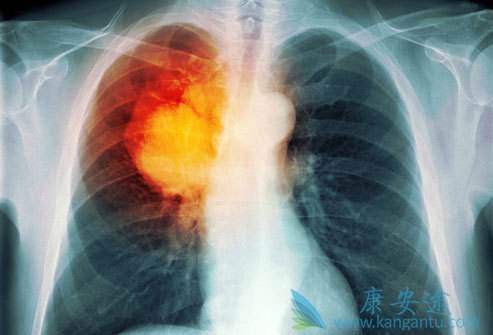

肺癌是一种高度恶性的肿瘤,在我国肺癌的发病率和死亡率都相当高。人们一旦确诊是肺癌以后,无论是对患者本身还是患者的家人带来巨大影响,对癌症的恐惧会使肺癌患者的整个家庭都笼罩在恐惧和死亡的阴霾中。很多肺癌患者或其家属都很关心,到底得了肺癌 ...

肺癌是目前各种肿瘤中发病率和死亡率最高的肿瘤,被称为肿瘤第一杀手。当肺癌发生骨转移,就意味着肺癌已发展到最晚的一期,治疗效果比较差,所以发现肺癌后,应接受专业医师指导,积极恰当地治疗,避免病情进一步发展。 肺癌骨转移症状 有哪些?疼痛是 ...

提到发热,大家的第一反应,是不是感冒了,病毒感染或者细菌感染,其实肺癌组织坏死也是可以引起发热的,我们称之为癌性发热,另外肺癌常常导致阻塞性肺炎,这也是引起发热的一大重要原因,这个时候,使用抗生素往往效果不佳。除了发热 肺癌早期有什么症 ...